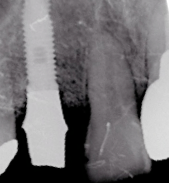

骨 の中に埋め込みますので骨のボリュームがない場合はできません。しかし現在骨のボリュームを人工骨などで、増やす移植技術も発達していますので、ケース によってはほとんどの場合、インプラントが可能になってきています。スマイルライン歯科ではそのような移植技術についても十分な検査のもとに行っておりますので、他院で不可能と言われた方でもご相談頂けたらと思います。しかし、タバコを多く吸われる方、糖尿病、骨粗しょう症の方はできない場合があります。

1.インプラントの手術 1,2時間程度で終わります。麻酔は局所麻酔です。

2.埋入したインプラントは縫合して骨に付く(オッセオインテグレーションといいます)のを待ちます。期間は3〜6ヶ月です。

3.骨が付いたら再度歯肉を切開して(2次オペれーションといいます)アバットメント(土台)をインプラントの上に付けて型をとります